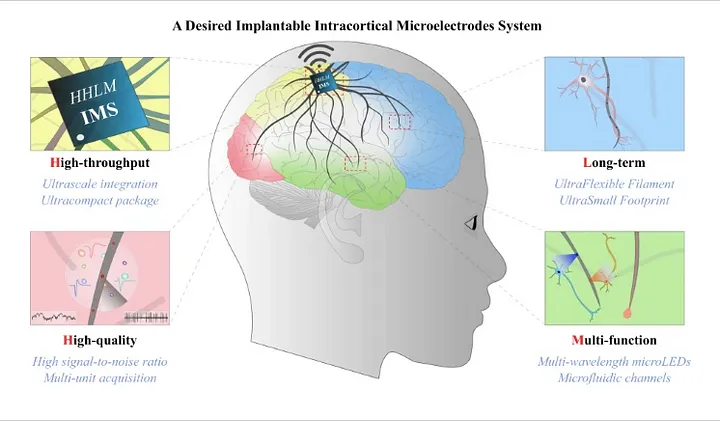

# 脑机接口

脑机接口是一种能解码大脑信号并将其转发到输出设备的设备,从而实现个人的预期功能。它有许多潜在的应用。Neuralink 和 ClearPoint Neuro 等公司一直致力于推动 BCI 的发展,使其能够用于假肢的运动,并将视觉想象转化为数字信号,应用领域非常广泛。那么,如果这项技术能够检测神经信号并以可视方式呈现,它是否能应用于疾病治疗呢?在跟踪认知功能进展和疾病转移方面,BCIs可以成为一种宝贵的工具。因此,临床医生可以就治疗策略做出明智的决定,从而实现以证据为基础、以患者为中心的护理。

脑机接口是如何工作的

脑机接口有4 个连续的组成部分:

信号采集:用于控制 BCI 系统的最常见信号是电信号。这就是输入。

特征提取:特征提取的目的是为电生理数据找到合适的表示方法(信号特征),以简化随后的分类或大脑模式检测。有许多特征提取方法可用于生物识别(BCI)系统,如振幅测量、频带功率、Hjorth 参数、自回归模型和小波。

特征转换/分类:分类器使用特征提取器记录的特征,将记录的信号样本归入大脑模式类别。

设备输出/应用界面:系统的反馈或输出最终被转化为可用于控制各种设备的适当信号。高级应用包括控制假肢设备和多媒体应用。

BCI的组成部分